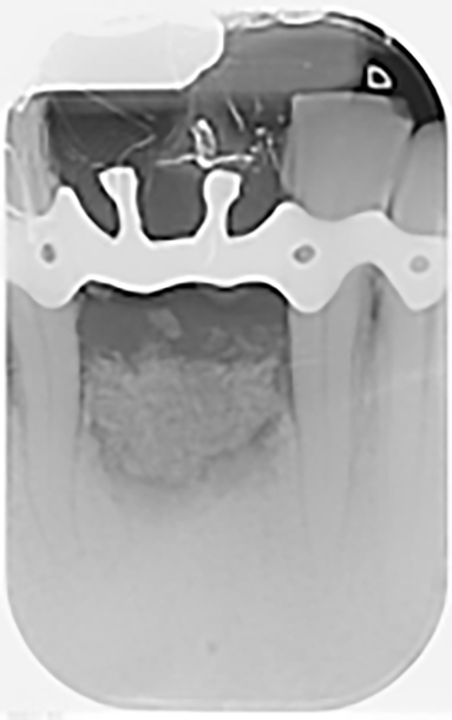

Si effettua la chirurgia implanto protesica guidata con mascherina (figura 8), si posizionano gli impianti 3.25 x 13 mm con un torque di 25 N (figura 9), si inseriscono i pilastri definitivi e si sutura (figura 10). Lo stesso giorno vengono ribasati e consegnati i provvisori solidarizzandoli con composito agli elementi 32-42 (figura 11).

Si effettua una radiografia di controllo dopo il posizionamento degli impianti e dei provvisori (figura 12).

Dalle radiografie (figure 1a, 3 e 11) si nota come ci sia stato un incremento del tessuto osseo.